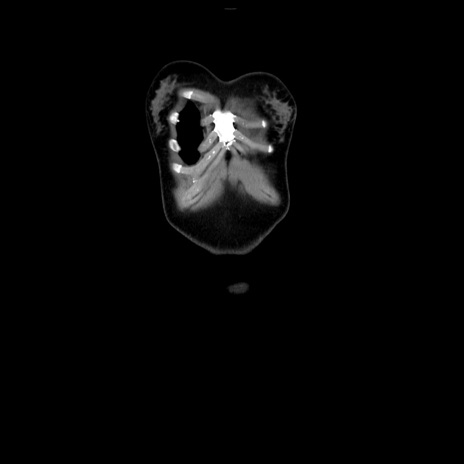

MRI(4日後)